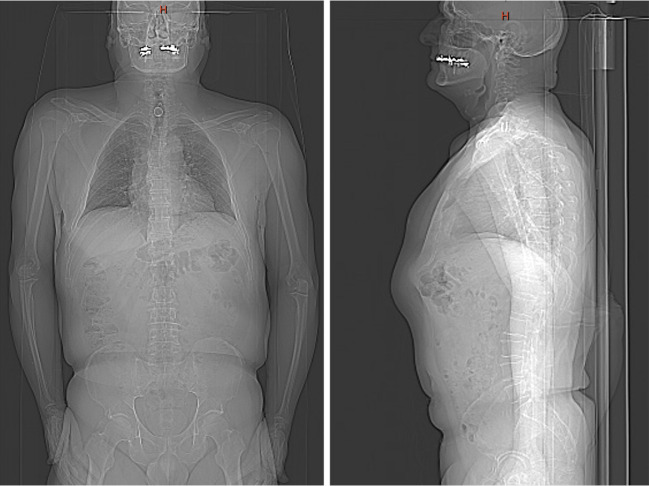

Background: The objective of this report is to present a case of two cervical spine artificial discs (Bryan Cervical Disk) that completely disappeared within 6 months as a result of a high-energy trauma more than 10 years after the initial surgery. Implant dislocation is a known complication in artificial cervical disc replacement. However, this report presents the case of an exceptional migration path with esophageal ingrowth and rectal excretion, not only for one artificial disc but for two at different times It highlights the need for long-term follow-up examinations after artificial cervical disc arthroplasty (ACDA).

Case description: The patient was seen in a Swiss outpatient spine center. He presented with a history of chronic laryngitis, which led to multiple ear, nose, and throat (ENT) diagnostic examinations without any cause being found. Migration of two cervical artificial discs was discovered incidentally in a cervical spine magnet resonance imaging (MRI), which was performed due to chronic myofascial pain in the lower extremities. The MRI showed anterior/retropharyngeal migration of one cervical disc. The second one could not be seen on the whole spine MRI. The complete patient history and radiographic findings were collected and reviewed. In addition, a whole-body computer tomography (CT) scan was done, and the patient was sent to an ENT center to rule out esophagus perforation and to verify the location of the two BRYAN © Cervical Disc.